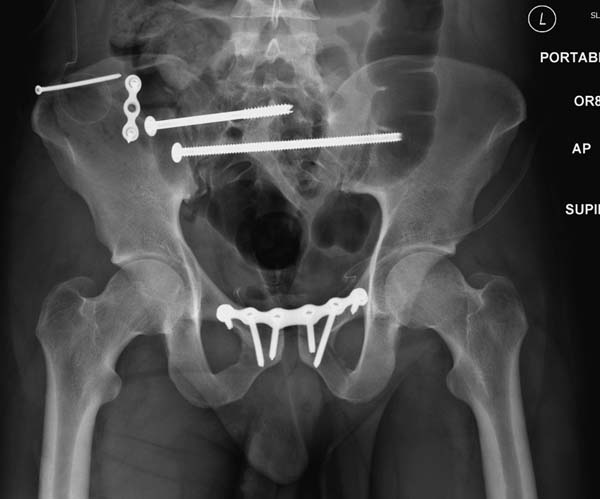

Но вам повезло, двумя винтами смогли зацепить и репонировать

переломо-вывих. Обычно такие переломы надо фиксировать спереди или сзади

пластиной или шурупом, т.е. создать дополнительную стабильность крыла,

кроме  перкутанной фиксации.

Здесь примеры фиксации с различными вариантами.... .